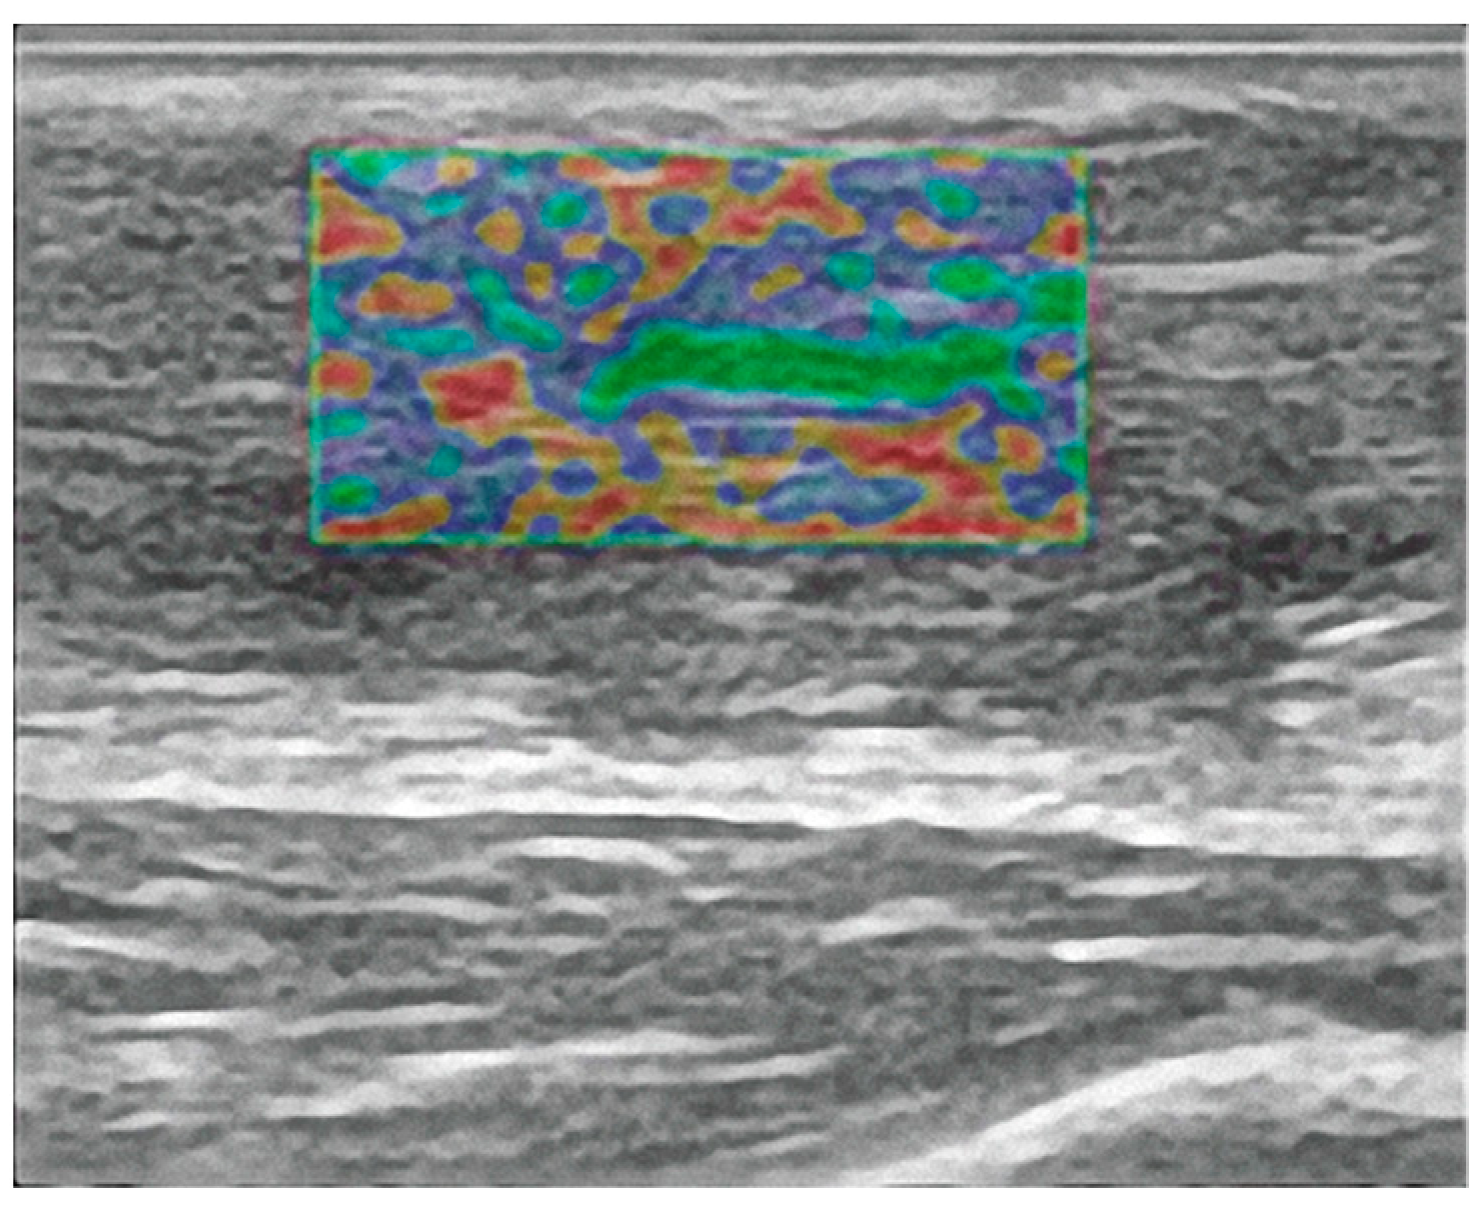

- Busilacchi, A.; Olivieri, M.; Ulisse, S.; Gesuita, R.; Skrami, E.; Lording, T.; Fusini, F.; Gigante, A. Real-Time Sonoelastography as Novel Follow-up Method in Achilles Tendon Surgery. Knee Surg. Sports Traumatol. Arthrosc. Off. J. ESSKA 2016, 24, 2124–2132. [Google Scholar] [CrossRef]

| Proximal | 90.0% (90.0–100.0%) | 90.0% (90.0–100.0%) | 0.74 |

| Medial | 80.0% (80.0–90.0%) | 75.0% (70.0–95.0%) | 0.18 |

| Distal | 80.0% (70.0–90.0%) | 80.0% (60.0–80.0%) | 0.54 |